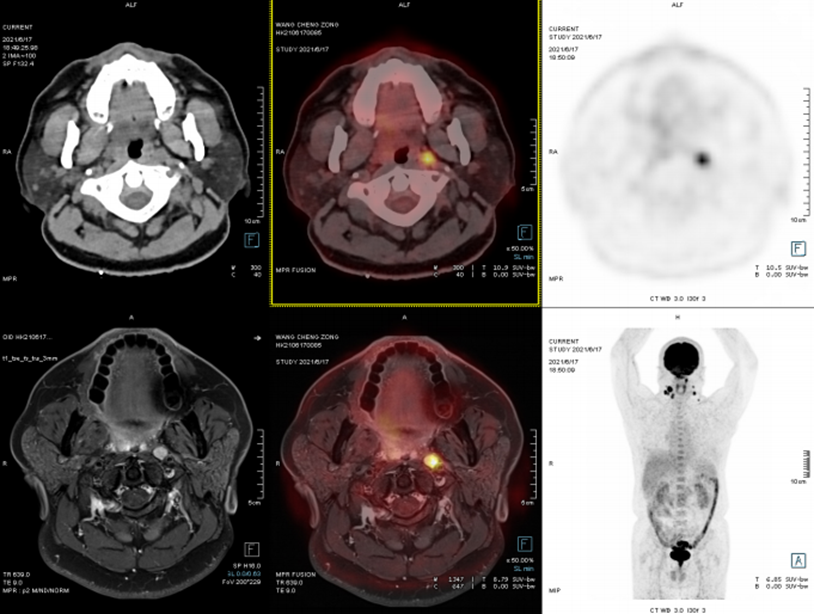

头颈部

案例:鼻涕带血半年余,2021-6-8喉镜:咽鼓管开口处新生物。为进一步明确诊断,行PET/CT-MR异机融合检查。

表现:右侧鼻咽壁不规则软组织增厚,FDG摄取增高,结合外院病理,符合鼻咽癌表现。两侧颈深上、中间隙及两侧咽旁间隙多发淋巴结转移。

病理:右鼻咽部非角化型分化性癌